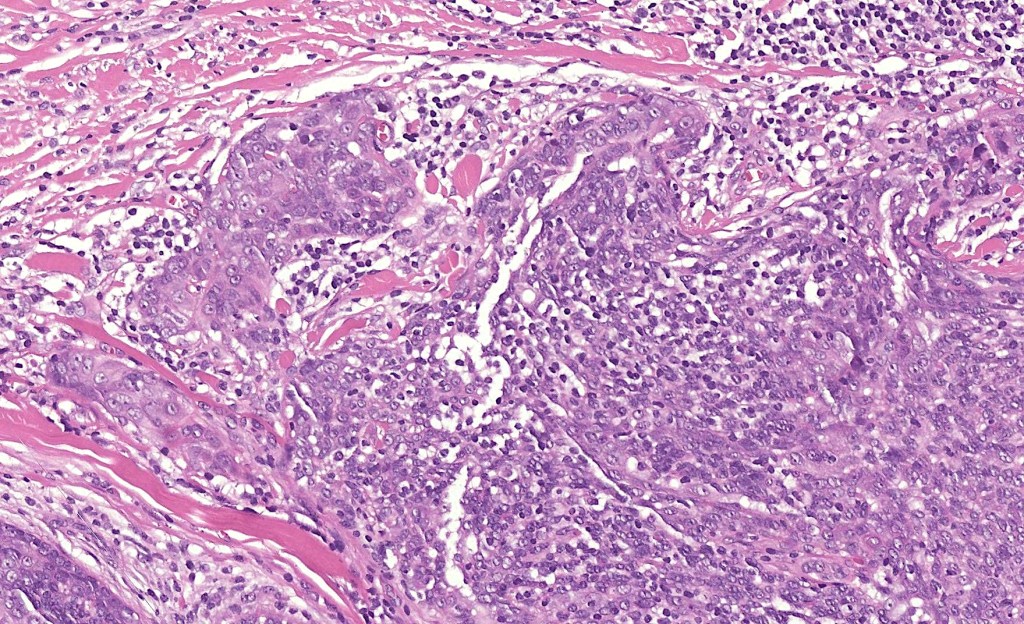

•Dermal generally circumscribed tumor nodule (less often it may show an infiltrative border)

•Syncytial epithelial component in nests, cords or sheets surrounded by an intense lymphoplasmacytic infiltrate

•Epithelial cells are large with abundant cytoplasm and vesicular nuclei with conspicuous nucleoli

•Marked mitotic activity, variable pleomorphism

•Absence of an epidermal connection